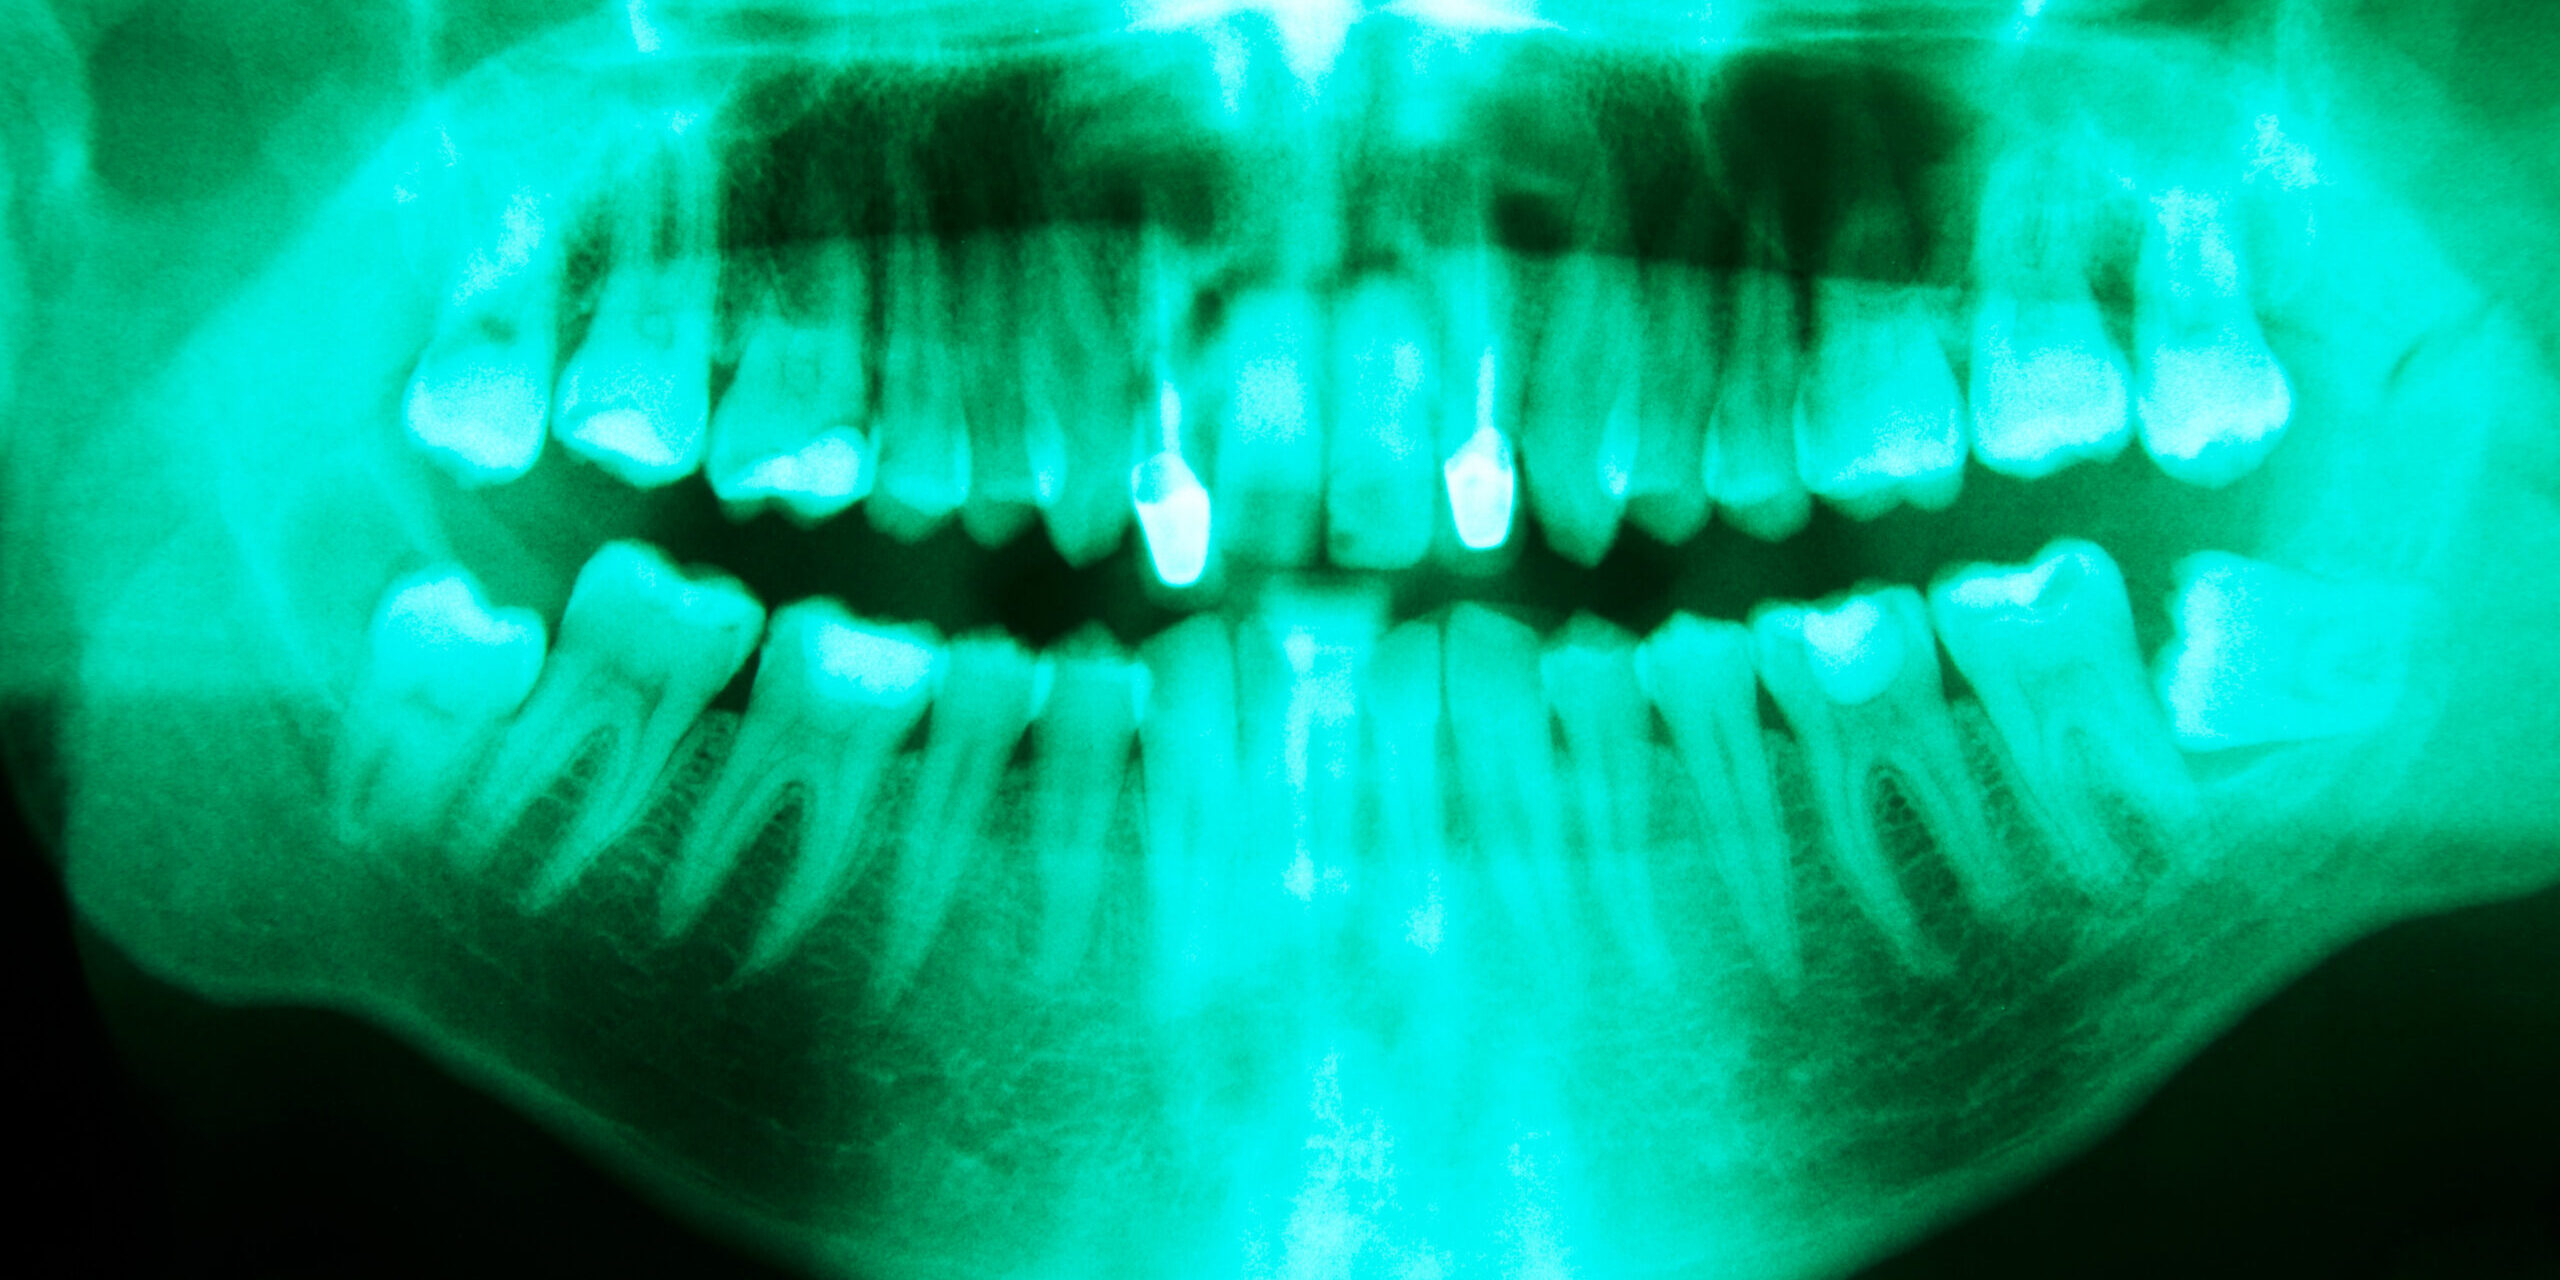

- Clear Explanations: I take time to explain the x-rays or 3D scans of your teen’s wisdom teeth. I’ll show you exactly how the teeth are positioned and what we’ll do. (If a picture’s worth a thousand words, an on-screen X-ray with my walkthrough is worth ten thousand.)

A: We understand the inclination to “wait and see,” especially if there’s no pain. However, wisdom teeth can cause silent damage before symptoms appear – such as pushing on other molars, causing cavities in hard-to-clean areas, or developing cysts[14]. The American Association of Oral Surgeons often recommends early evaluation and removal, usually in the late teens, because the roots are not fully formed and the bone is more forgiving, leading to easier removal and recovery[15]. Waiting until they do hurt can mean a more complicated procedure (and having pain or infection to deal with). In Bixby, we commonly take out wisdom teeth in high school or early college years as a preventive measure. Of course, every case is unique – which is why a consultation (with a panoramic X-ray) is the best way to determine timing. If the teeth look like they may never be an issue, we will tell you that too. Our philosophy is to treat based on the best evidence and the patient’s individual situation.